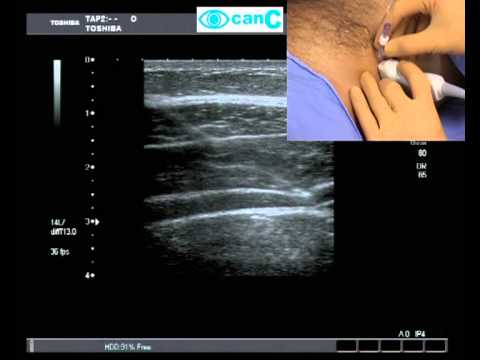

A linear transducer is placed alongside the lower margin. There are several different approaches for ultrasound guided tap block such as lateral posterior and subcostal approaches. The innervation to abdominal skin muscles and parietal peritoneum will be interrupted.

Traditionally the posterior tap block is performed at the triangle of petit. The transverse abdominis plane tap block is a peripheral nerve block designed to anesthetize the nerves supplying the anterior abdominal wall t6 to l1. For the lateral tap block a linear transducer is placed in.

12 this is an area bounded by the latissimus dorsi muscle posteriorly the external oblique muscle anteriorly and the iliac crest inferiorly the base of the triangle. It has a high margin of safety and is technically simple to perform especially under ultrasound guidance. A needle is inserted perpendicular to all planes looking for a tactile endpoint of two pops.